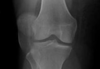

Knee XR: gout vs pseudogout